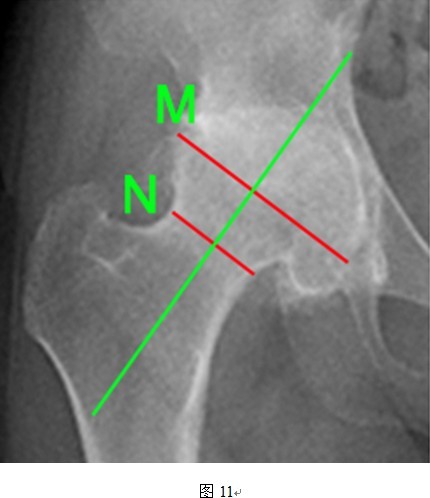

THRA的假体设计要求,头颈比为1.2:1的髋关节对于THRA手术最为适合,但是本组数据达到平均1.47(图11所示病例为典型头颈比增大),可能与DDH的病理特点有关。大头颈比情况下,股骨颈相比之下则显得纤细,造成术后股骨颈人为缩窄现象。目前认为股骨颈骨折主要与股骨颈上部切迹和股骨假体内翻放置有关,尚未有文献提及宿主头颈比、人为股骨颈缩窄对术后假体存活、股骨颈骨折的影响,二者间的联系尚待进一步证实。

④头颈比:M/N的数值(M线为股骨头直径,N线为股骨颈直径);

DDH患者股骨头往往变扁增宽,图中股骨头直径与股骨颈直径的比例(M/N)远远超过1.2:1。